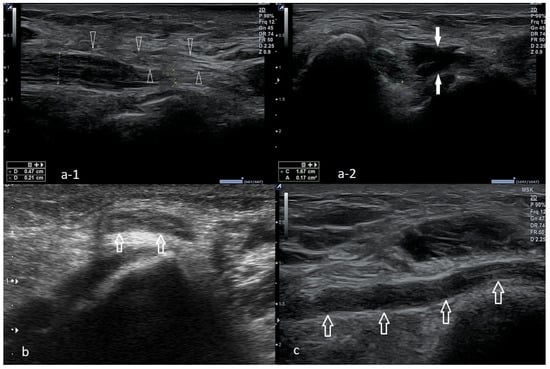

4.1. Cubital Tunnel Syndrome and Ulnar Neuritis

4.2. Snapping Triceps with Ulnar Neuritis

4.3. Ulnar Nerve Compression Caused by Anconeus Epitrochlearis